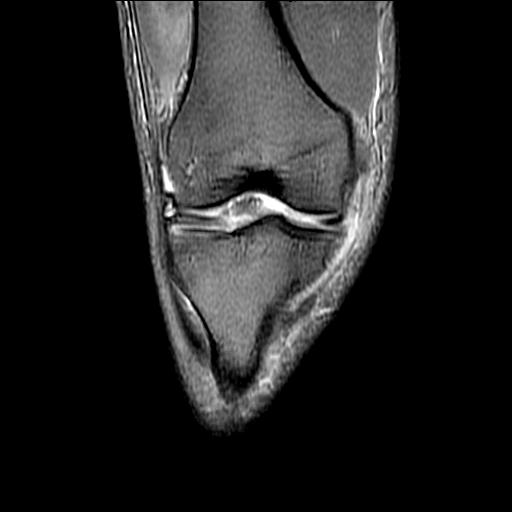

标题: MRI1265:男性40岁,右膝关节 [打印本页]

标题: MRI1265:男性40岁,右膝关节

40岁男性,右膝关节外伤,x光平片示,髁间隆突撕脱骨折。

1、前交叉韧带撕裂;

2、外侧半月板后角撕裂;

3、关节腔积液。

前交叉韧带撕裂,关节腔积液.

半月板1-2级损伤   前交叉韧带撕裂伤   关节腔少量积液  诸骨未见新鲜外伤性改变

髁间隆突撕脱骨折;内侧副韧带损伤。

内侧副韧带撕裂及关节腔积液是肯定的,但是前交叉撕裂确定吗?会不会有容积效应的因素,因为前一张前交叉显示清楚,连续性良好,且较光滑。请问楼主有关节镜支持吗?我们医院也经常有这样的患者,但苦于没有关节镜,而无法对照、证实(除非完全断裂),出现了不同的诊断结果只能毫无意义的争论。

1、前交叉韧、内侧副韧带撕裂;

3、关节腔积液。4、髁间脊撕脱骨折。

除了关节积液外并无韧带撕裂,acl胫侧附着点有2束,正常情况下脂肪信号。此病例应加做压脂像以便观察是否有骨损伤。